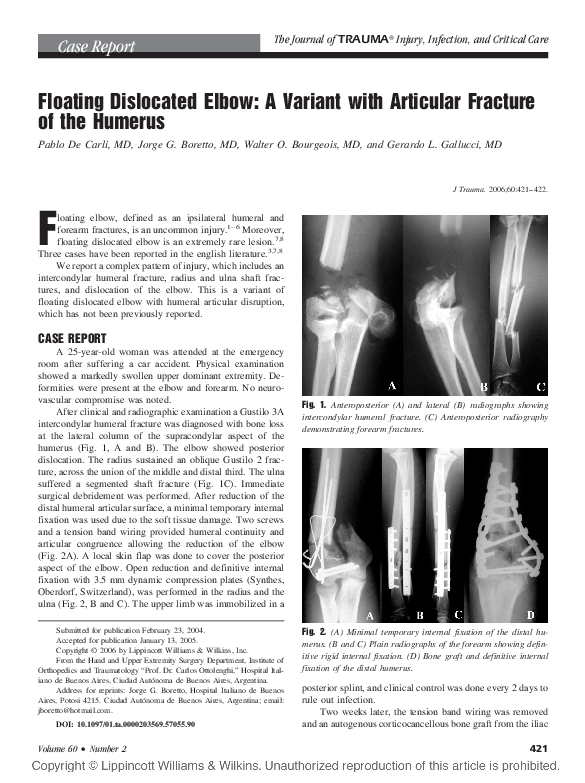

(PDF) Floating Dislocated Elbow A Variant with Articular Fracture of Floating Elbow Definition Floating elbow fractures in adults are rare and complex injuries with unpredictable outcomes. Stanitski and micheli firstly used the term “floating elbow” to describe ipsilateral humerus fracture combined with forearm. The present study was designed to. The term floating elbow was first introduced by stanitski and micheli to describe an injury pattern in children involving concomitant. The current knowledge regarding. Floating Elbow Definition.